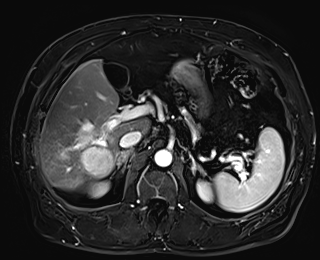

79 M with PMH of CKD, HLD, prostate cancer s/p prostatectomy + radiation presenting with feelings of fogginess, upset stomach, and diarrhea. Originally worked up at OSH, imaging concerning for a hepatic mass.

AST 112, ALT 34, Alk Phos 202, CEA 2, CA 19-9 4

69 M with PMH of HCV cirrhosis & HCC s/p resection in 14 years ago presenting today for a screening ultrasound.

CMP wnl, AFP 5